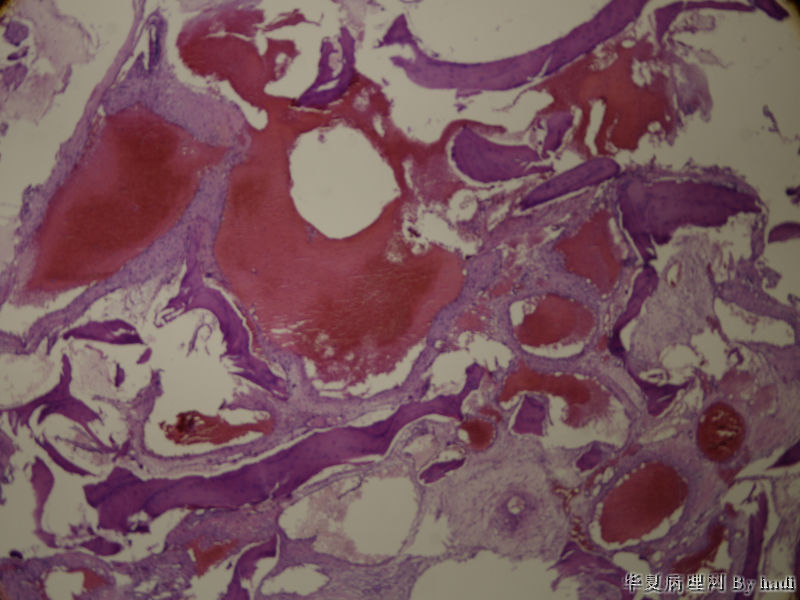

• 鼻腔肿瘤图3

图3